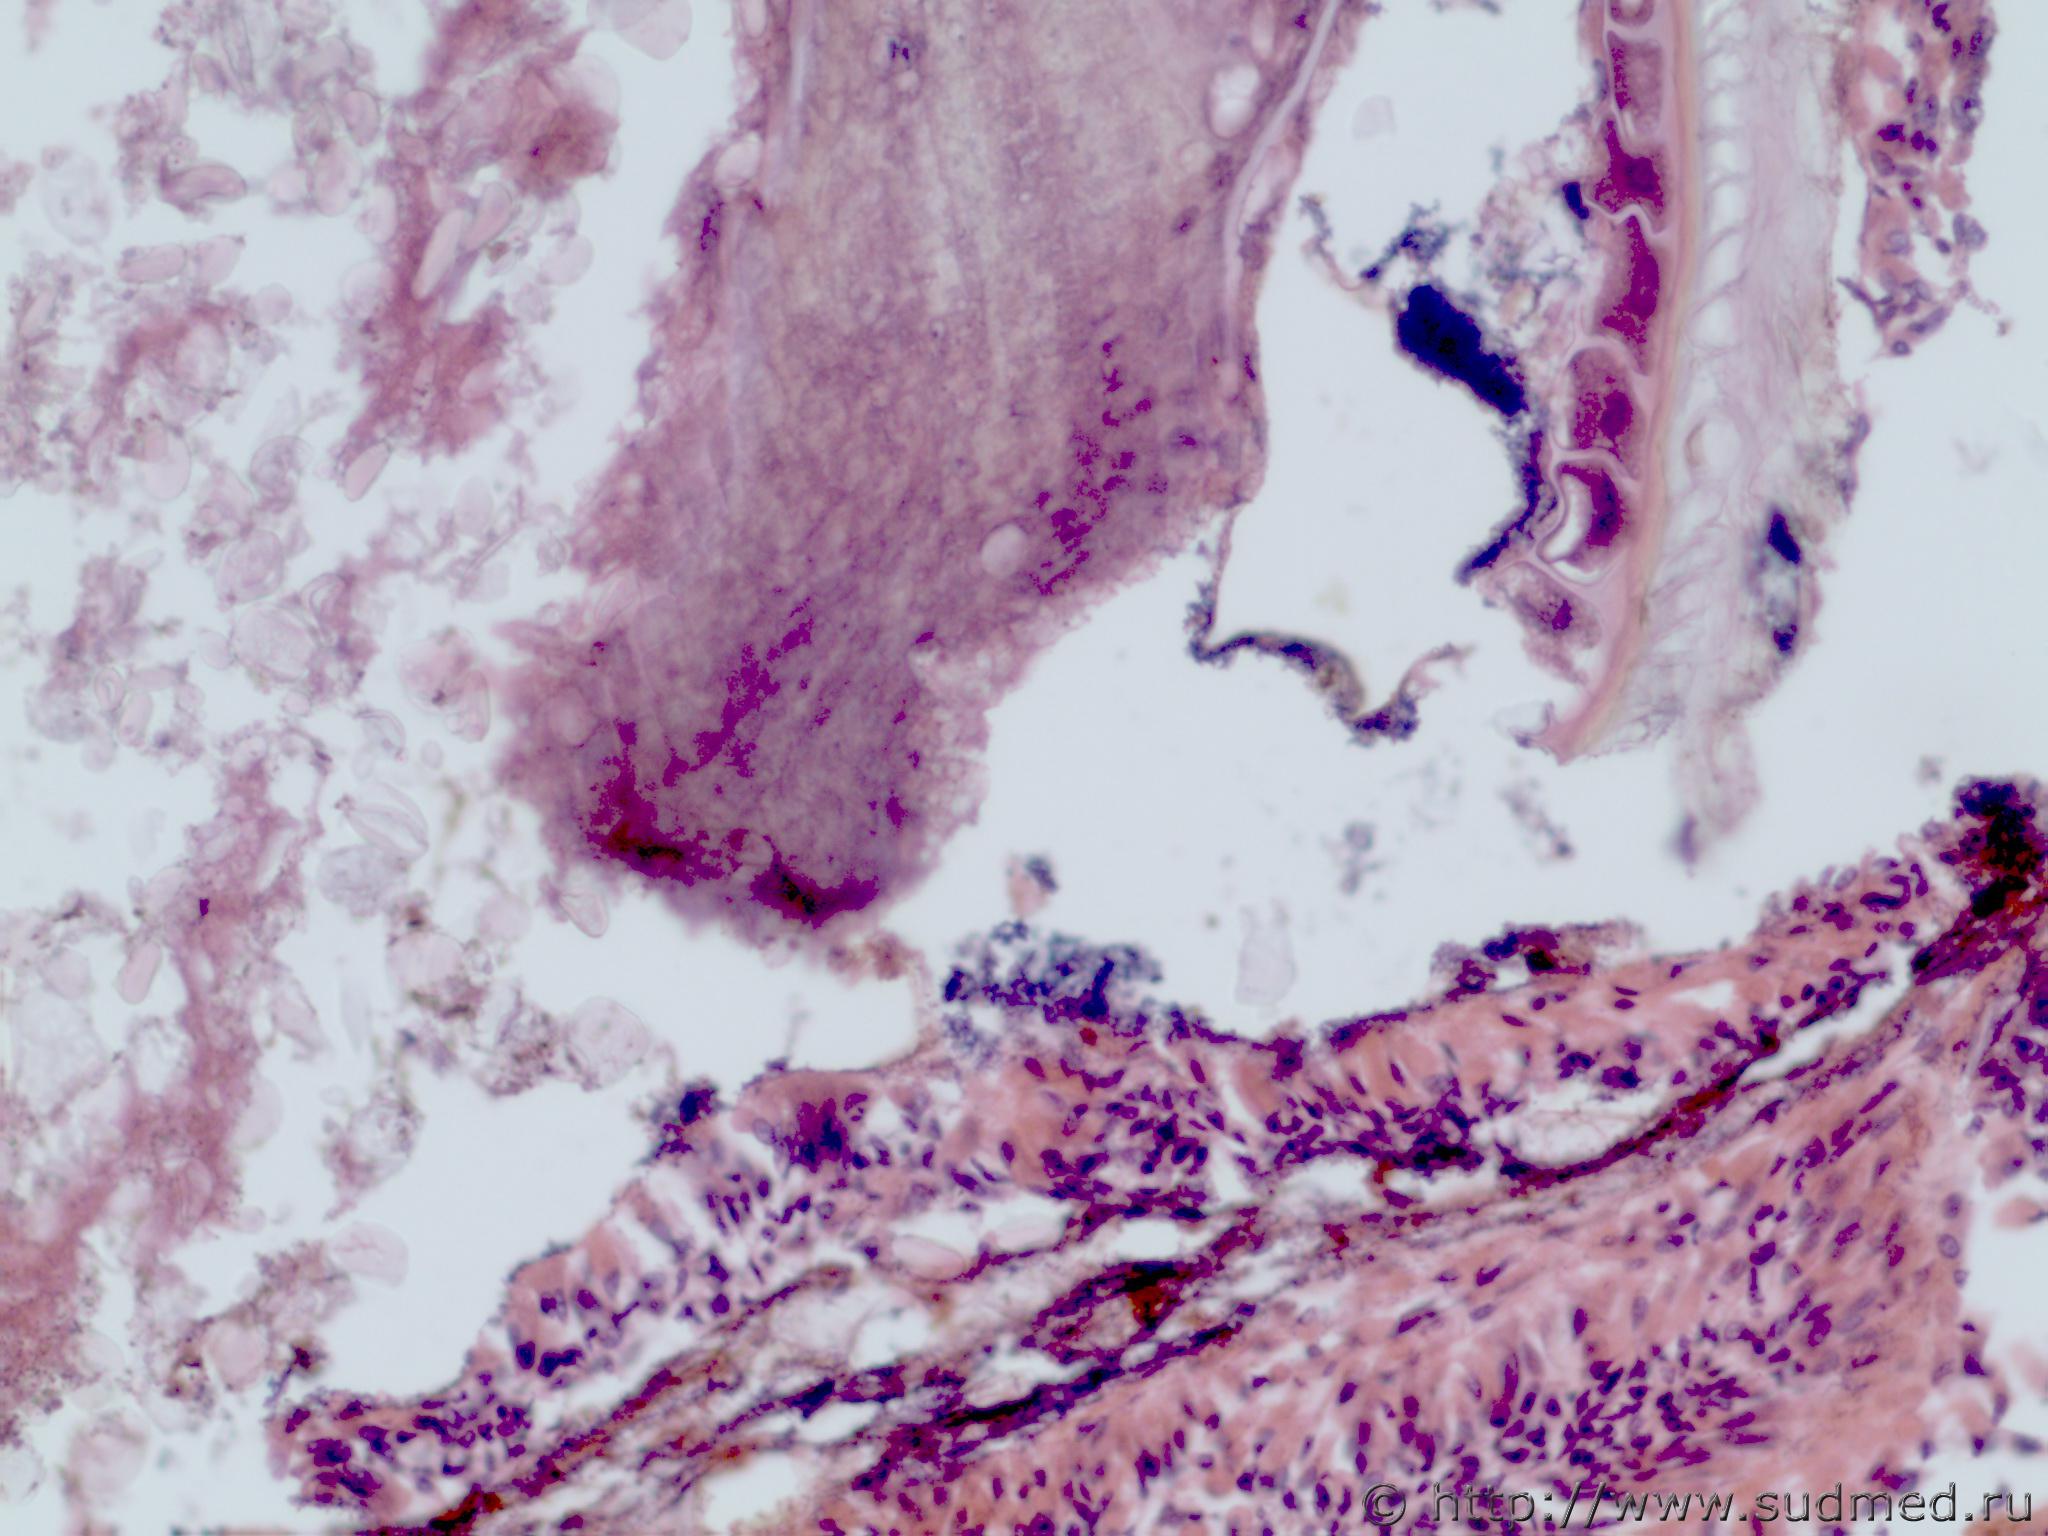

Аспирация ЭОВ (роговыми чешуйками)